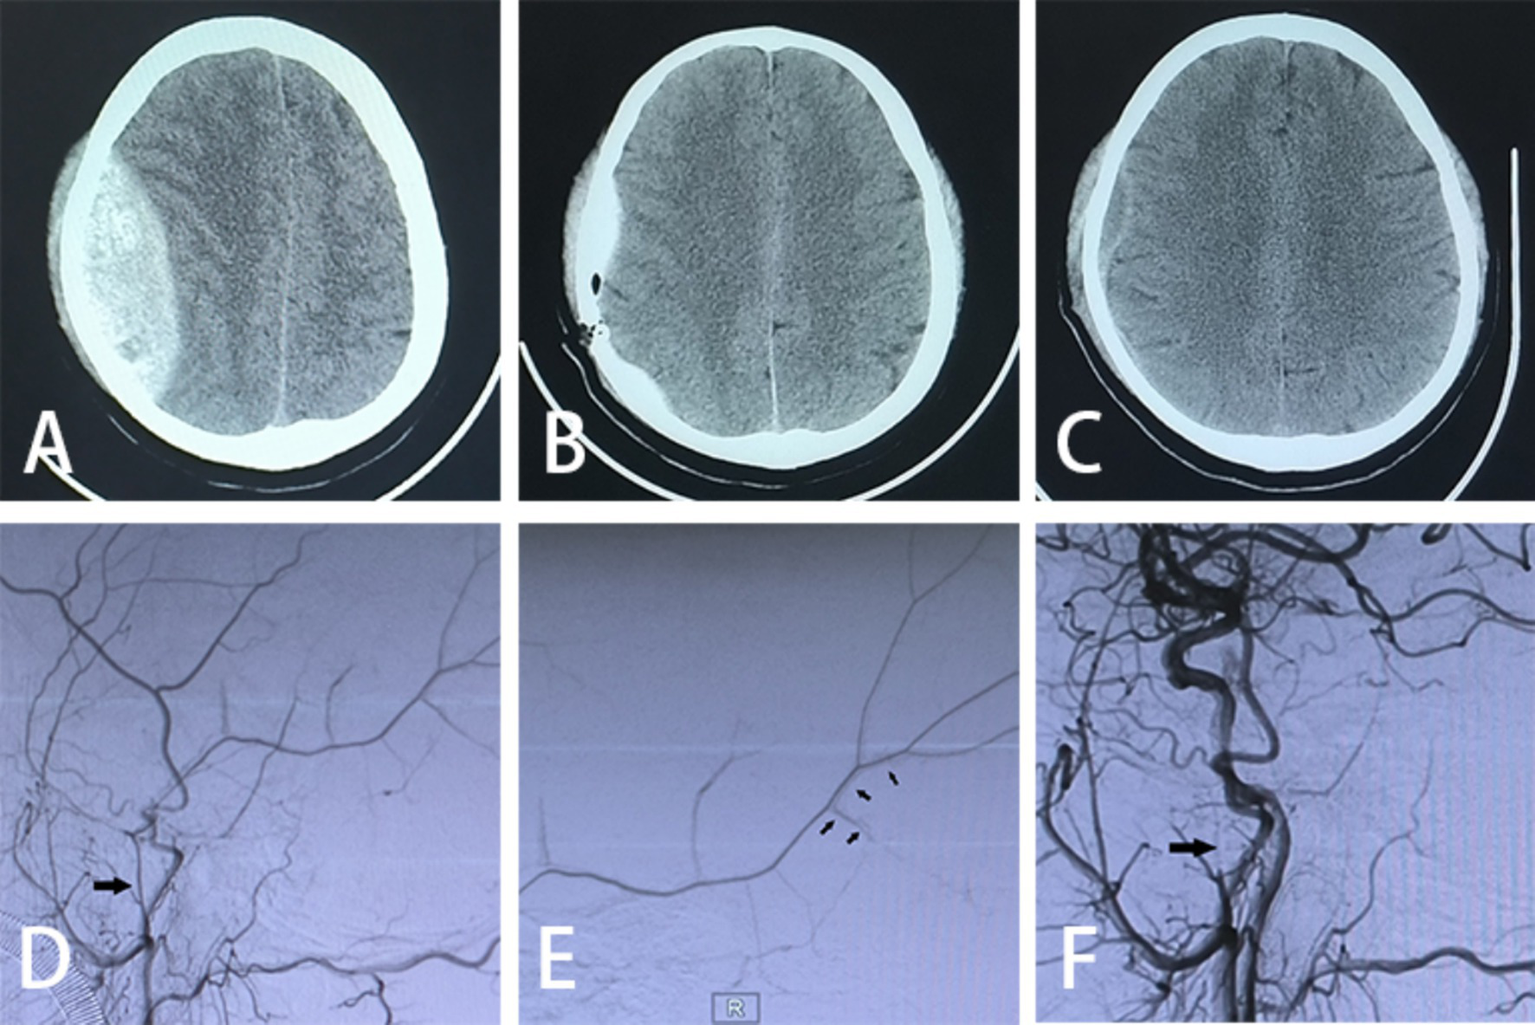

Figure 2

Imaging data. (A) Preoperative cranial CT scan; (B) postoperative cranial CT scan on day 1; (C) postoperative cranial CT scan on day 21; (D) preoperative DSA exhibiting MMA abnormality (large arrows); (E) intraoperative DSA demonstrating contrast spillage (small arrows); (F) postoperative DSA indicating undeveloped MMA (large arrows pointing to the spring-coil embolization).